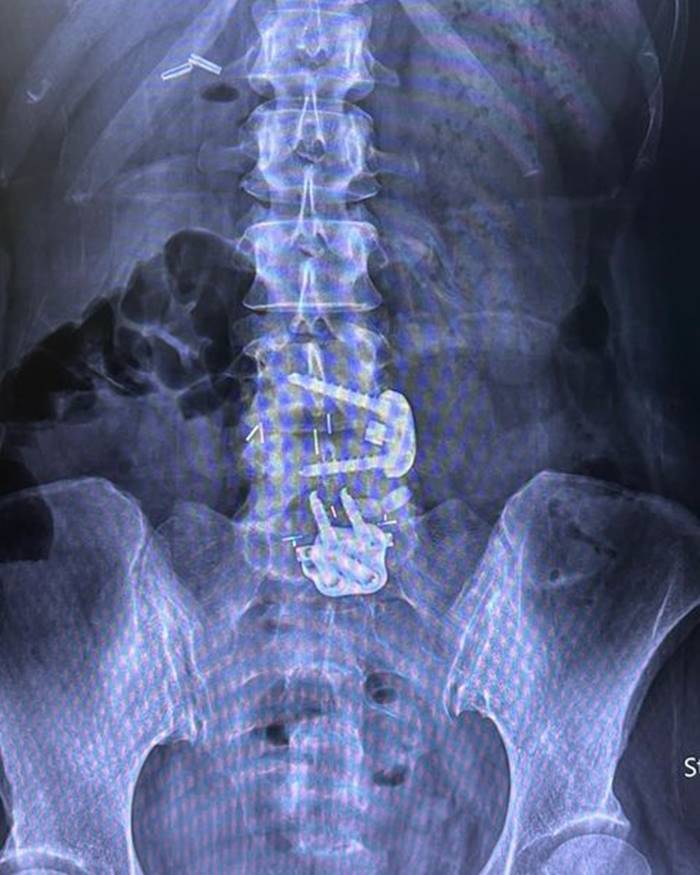

โดยเมื่อวันที่ 28 กรกฎาคม 2565 มาดามหนุ่ย ได้โพสต์ภาพเอกซเรย์กระดูกที่ถูกใส่เหล็ก พร้อมข้อความว่า "อยากขอเตือนเพื่อน ๆ นะคะ ว่าถ้าออกกำลังท่าไหนแล้วรู้ตัวว่าไม่ไหวก็ให้บอก trainer ค่ะ อย่าฝืนทำ เพราะลงท้ายอาจจะต้องผ่าตัดแบบหนุ่ย.. trainer ให้ทำ squat ที่หนุ่ยก็หันไปบอกแล้วว่าหนักไปทำไม่ได้เค้าก็ยังให้ทำ ผลคือหมอนรองกระดูกปลิ้น ต้องผ่าตัดใส่เหล็กตามภาพเลยค่ะ..ตอนนี้ก็ต้อง slowlife ไป 4-5 เดือน"